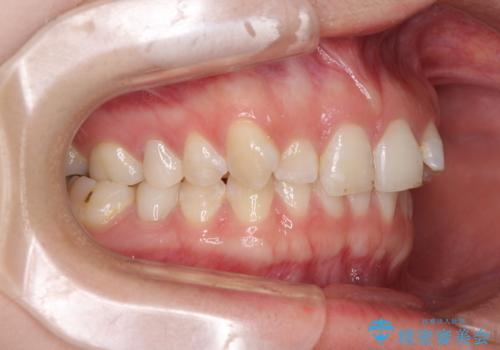

- 前歯の歯列不正を気にして来院された患者様です。

インビザラインでの矯正治療を希望されていましたが、奥歯の咬み合わせがインビザライン単独では改善困難と判断されたので、補助装置を併用することとしました。

まずは裏側の装置やワイヤー矯正を用いて歯列幅の狭い上顎を側方に拡大しつつ全体を後方に移動させ、その後インビザラインにて歯列を整えることとしました。